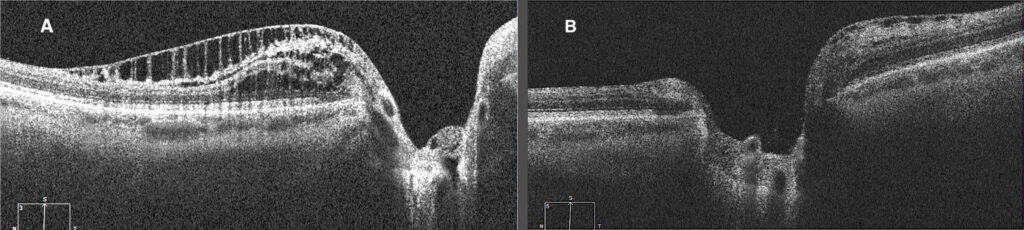

Figure 3. A) OCT of the OS of PPRS inferior to the ONH at onset (four years prior to the current exam). B) OCT of the OS of resolved inferior PPRS with a new onset PPRS superior to the ONH (taken during the current exam).

A cross-sectional examination conducted in 2021 used spectral-domain OCT (SD-OCT) and Bruch’s membrane opening (BMO) as the anatomical boundary around the optic nerve head (ONH) to determine the pathogenesis of PPRS.1 If the proximal edge of the PPRS is behind the BMO, then the layers of the retina which would likely be affected are the ganglion cell layer, inner plexiform layer, and retinal nerve fiber layer.1 PPRS can also present with vitreous traction followed by a posterior vitreous detachment, thus the proposed etiology of the PPRS in these cases is mechanical vitreous traction on the retina.1 If the proximal edge of the PPRS is past the BMO, it will likely affect the inner nuclear layer, outer plexiform layer, and outer nuclear layer.1 The proposed etiology of this type of PPRS is secondary to the invasion of liquified vitreous through compromised Bruch’s membrane to the underlying retinal tissue.1 It is suggested that the micro-holes found in glaucomatous eyes due to Müller cell dysfunction leads to vitreous fluid invasion to the RNFL resulting in the formation of PPRS.1,2 The OCT of the PPRS found in the patient’s left eye, shows that the proximal edge is past the BMO (Figure 3A). This suggests that the PPRS formed as a result of the vitreous leaking through Bruch’s membrane and into the retinal tissue below it.